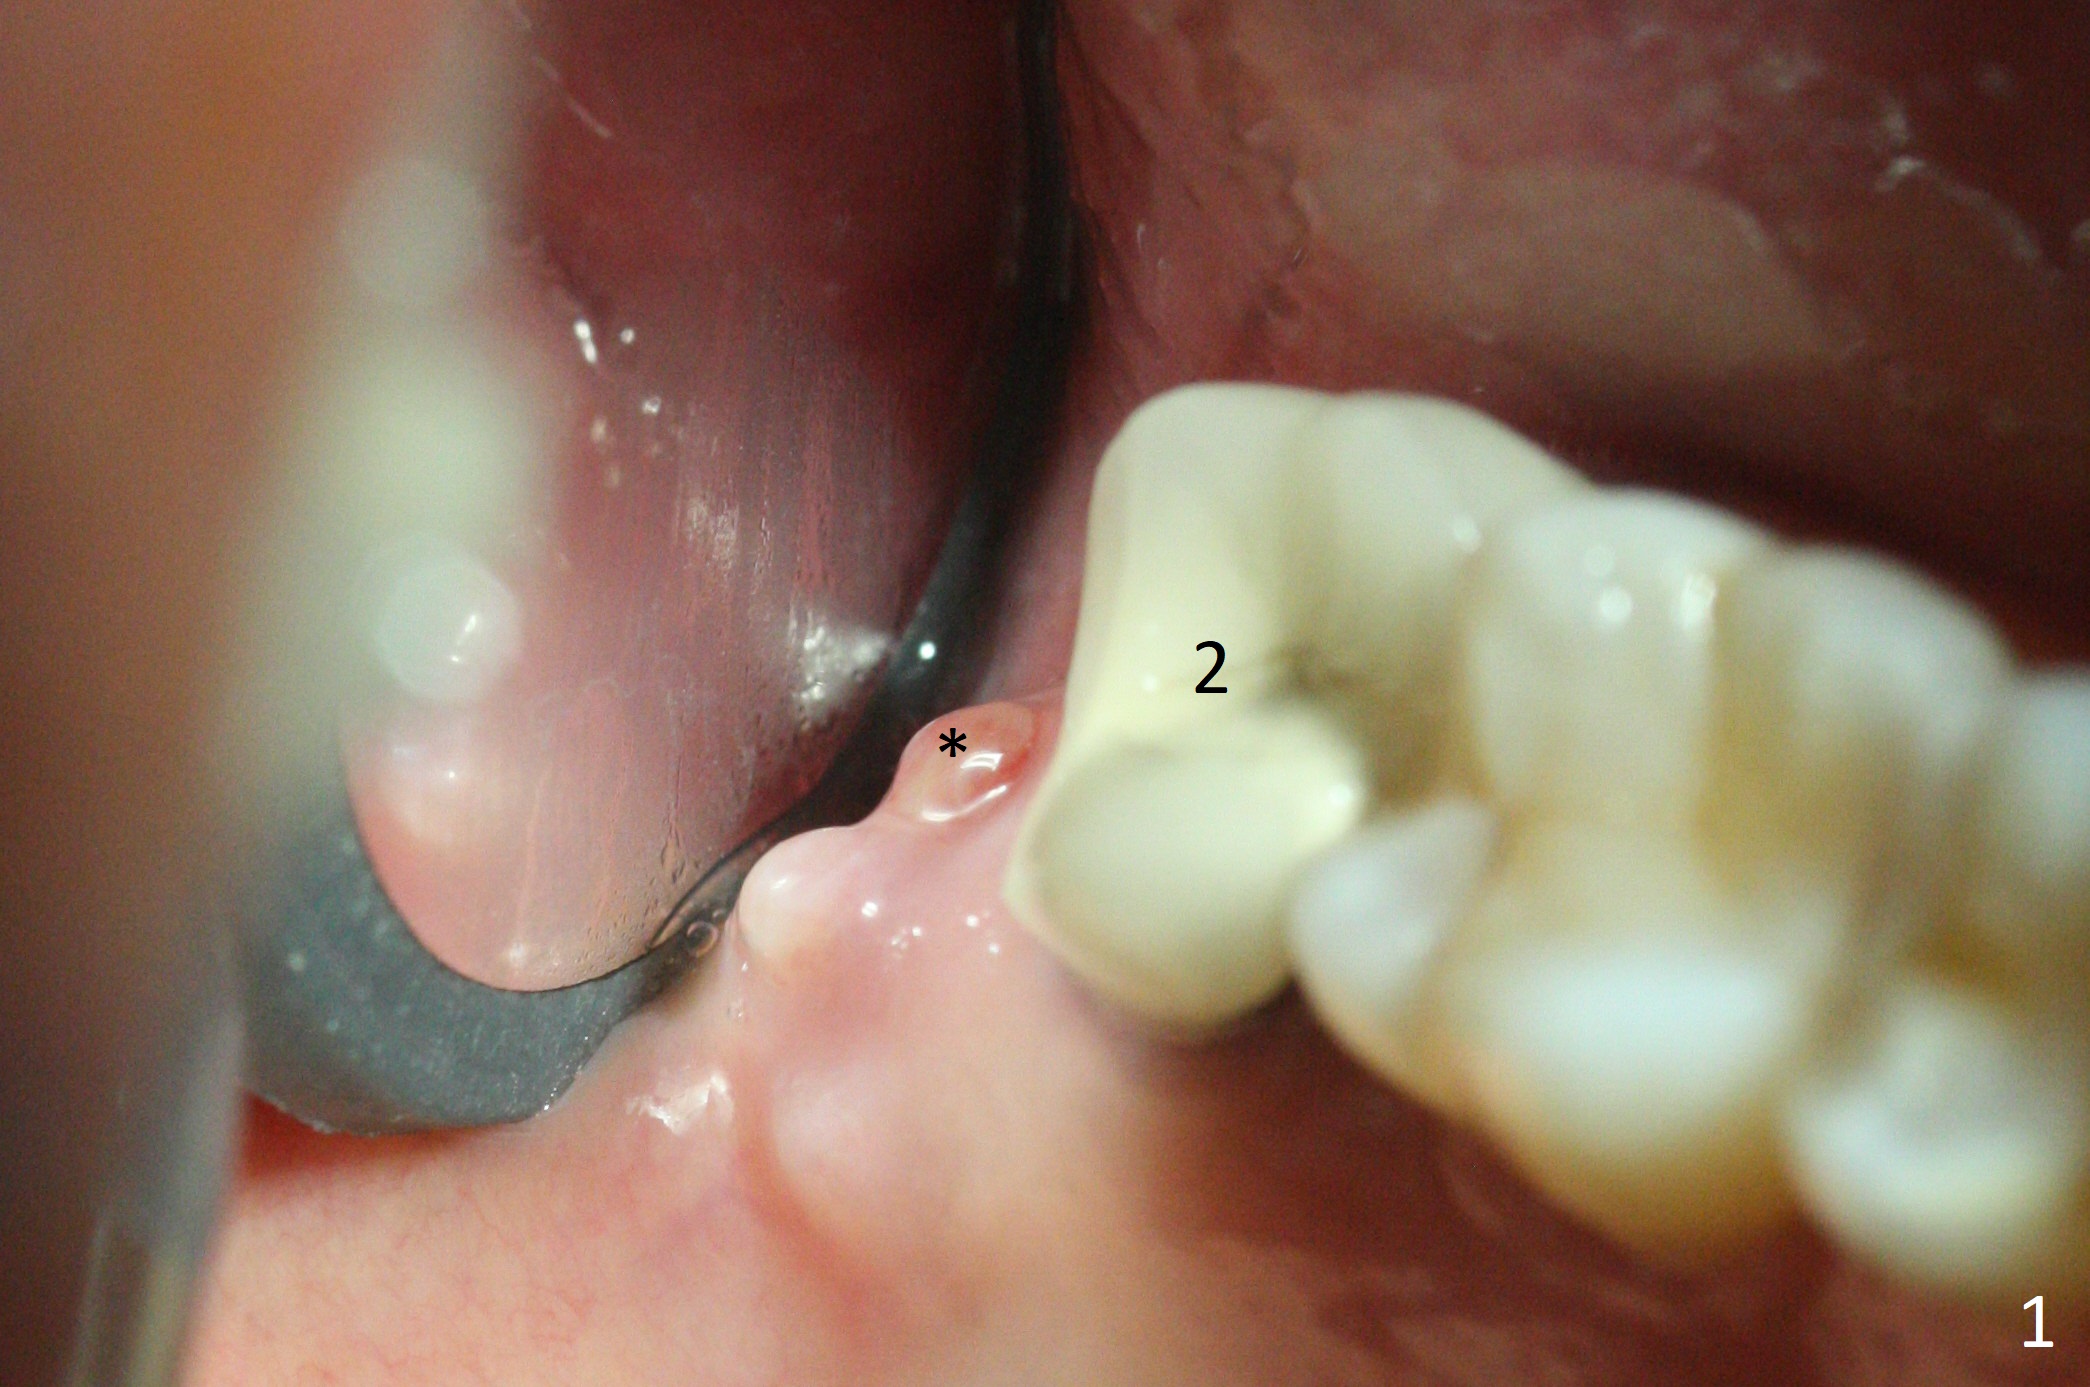

There is a fistula distal to the tooth #2 with deep pocket distopalatally (Fig.1 *), corresponding to palatal root fracture (Fig.2). There is a septum (Fig.3 S) between the buccal (B) and palatal (P) sockets. Osteotomy is initiated in the center of the septum (Fig.4 black circle). In fact the center of the socket is buccal (red circle), in which osteotomy should have been established because of the presence of the distopalatal bony defect associated with the root fracture and the distal fistula. The less ideal initial osteotomy leads to palatal placement of the implant and abutment (Fig.11 vs. 12).